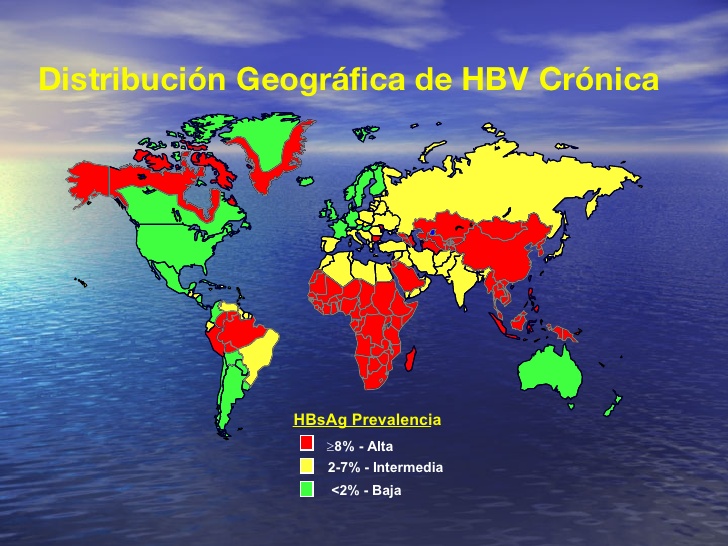

2.1) Distribución geográfica

La máxima prevalencia de la hepatitis B se registra en el África subsahariana y Asia oriental, regiones en las que entre el 5% y el 10% de la población adulta está infectada de forma crónica. También hay tasas elevadas de infección crónica en la cuenca del Amazonas y en partes meridionales de Europa oriental y central. Se calcula que entre un 2% y un 5% de la población del Oriente Medio y el subcontinente indio padece infección crónica. En Europa occidental y América del Norte menos del 1% de la población padece infección crónica.